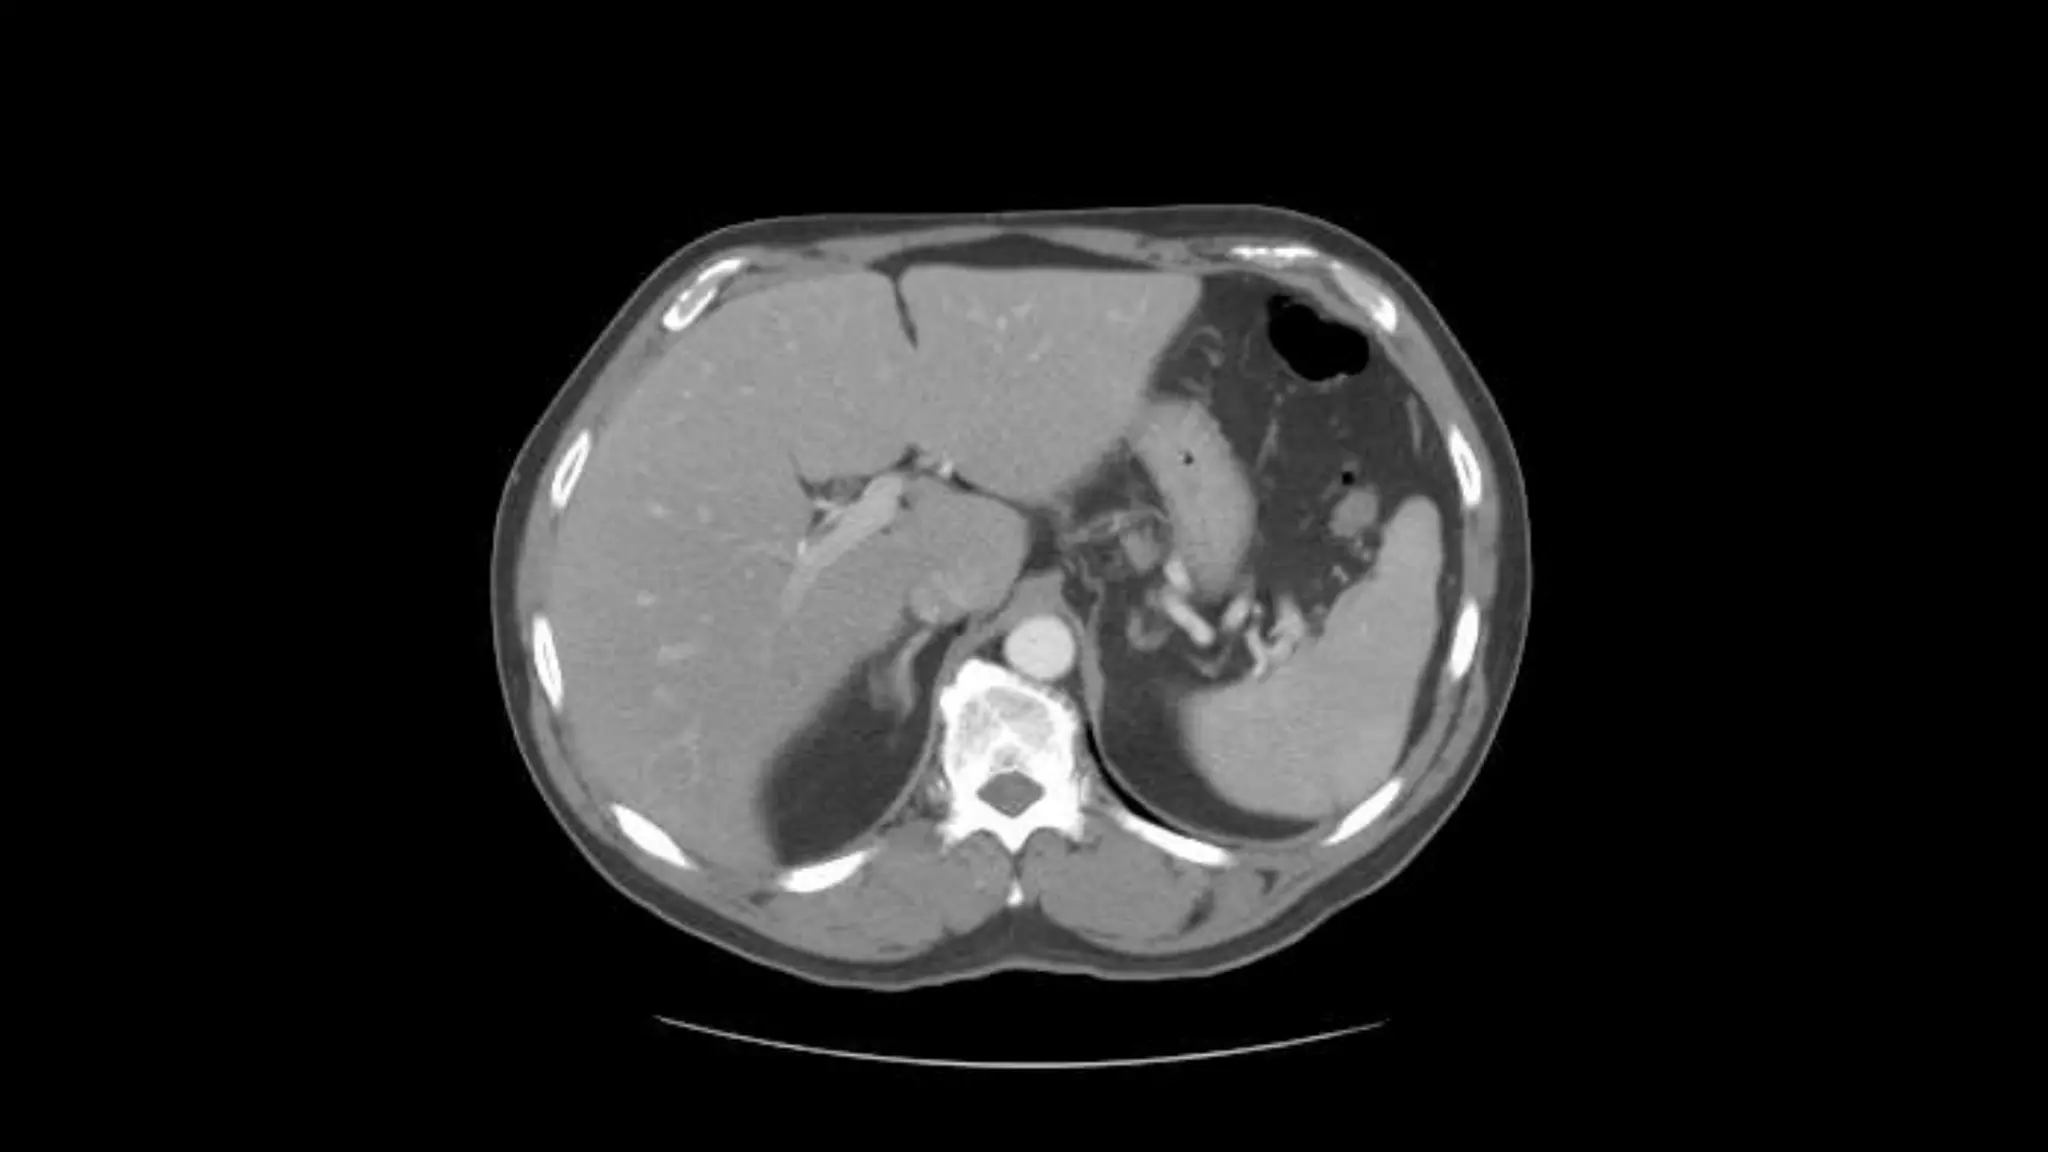

This is an excellent image of the right, middle and left hepatic veins draining into the Inferior

Vena Cava. Don’t confuse this structure with the IVC, this is the esophagus at the level of the

Lower esophageal sphincter, page up and down to confirm this.

The outline of the Inferior Vena Cava is more

distinct in this image.

Portal Vein Branching into the Liver

Liver

Stomach